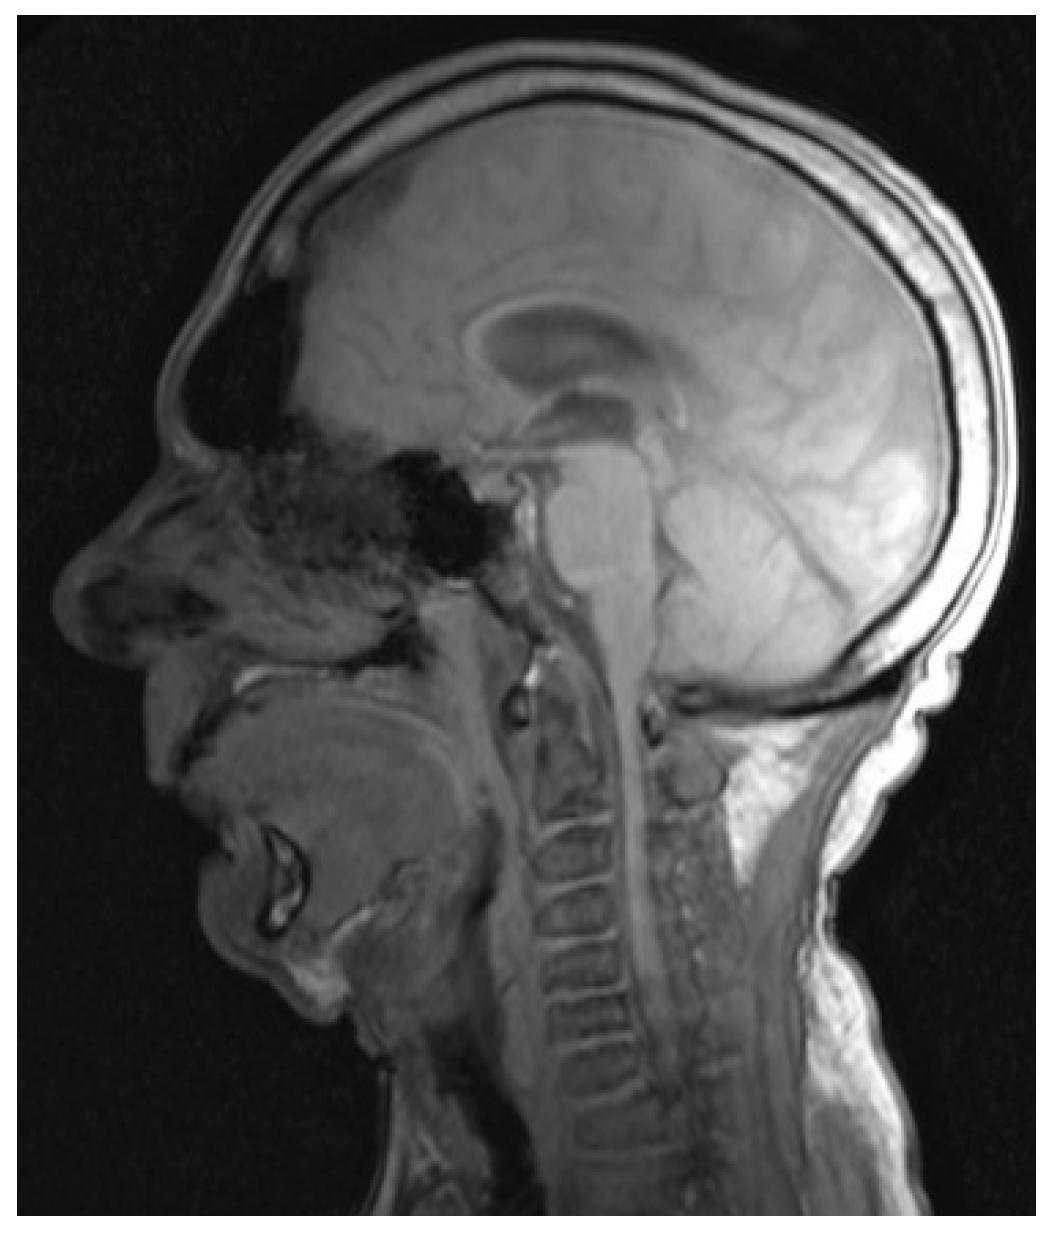

3.2. Cross-Sectional Imaging

3.3. 3-Dimensional Reconstruction (3D) and Virtual Endoscopy (VE)